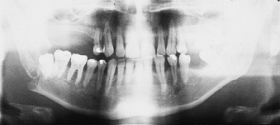

The primary purpose of the consultation is the outpatient follow-up treatment and care of patients who have undergone surgery following bone injuries to the upper and/or lower jaw. In addition to patients with fractures of the facial skull, patients with injuries to the teeth and facial soft tissues are also followed up.

Osteosynthesis procedures are performed at our clinic according to modern international standards. Mini and micro plates made of titanium and special medical steel are used to stabilize the fractured bones. Especially for the treatment of temporomandibular joint fractures a joint plate was developed in our clinic. The development and application of resorbable osteosynthesis materials is at the same time a research task of the clinic.